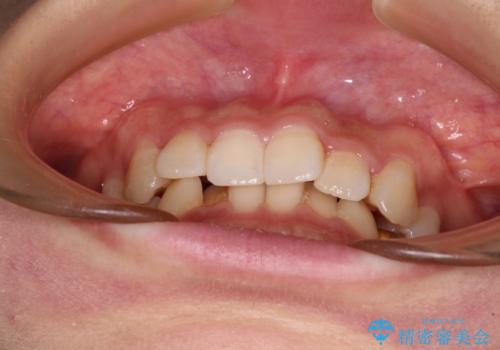

- 前歯のデコボコと深い咬み込みを気にして来院された患者様です。

インビザラインを用いて、前歯の叢生を解消するとともに、深い咬み合わせ(ディープバイト)を改善していくこととしました。

奥歯を後方に直立させることで深い咬み合わせを改善を図り、隠れていた下顎前歯が見えるほどになりました。